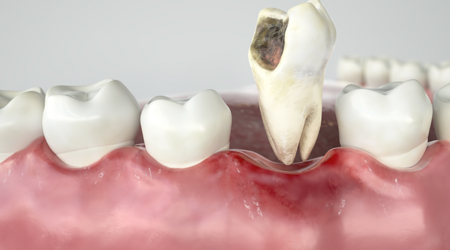

Non Surgical Tooth Extraction 1000 15

Procedure INR US

Surgical Tooth Extraction 4000-10000 60-155

ROOT CANAL TREATMENT 4500-6000 70-90

Treatment INR US